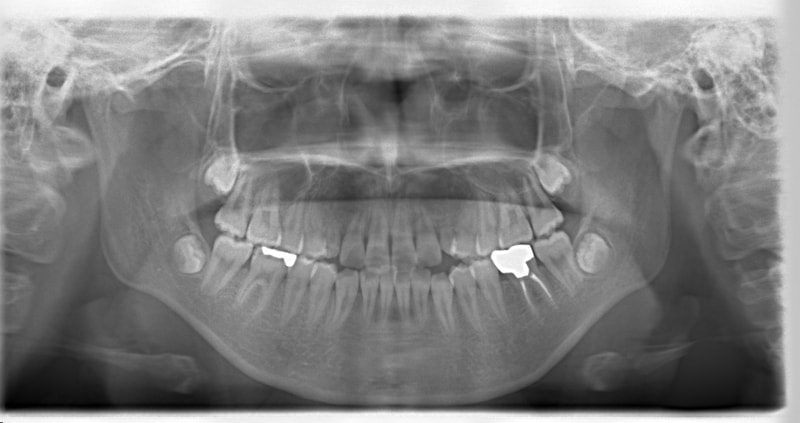

先天欠如歯両側上顎3番

治療法:フルパッシブブラケット:T21

治療開始時